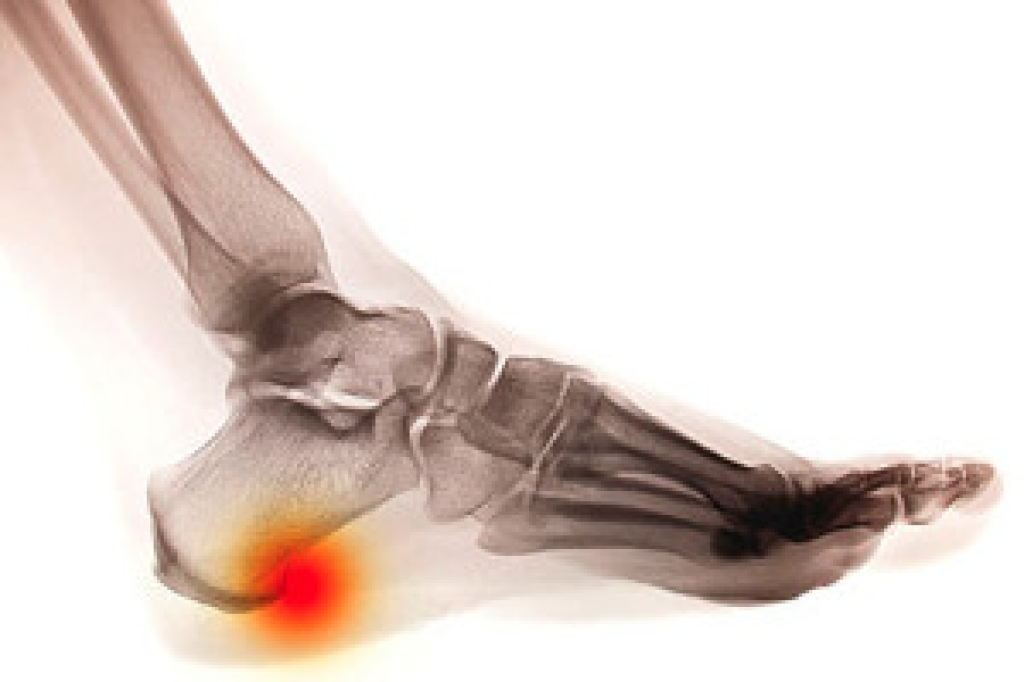

Ingrown Toenails

Ingrown toenails occur when a toenail grows sideways into the bed of the nail, causing pain, swelling, and possibly infection.